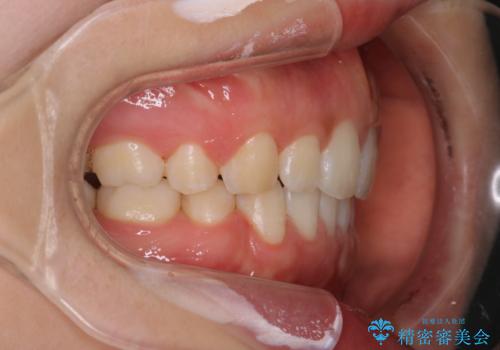

前歯の隙間を閉じたい 口元も下げたい ハーフリンガルによる抜歯矯正